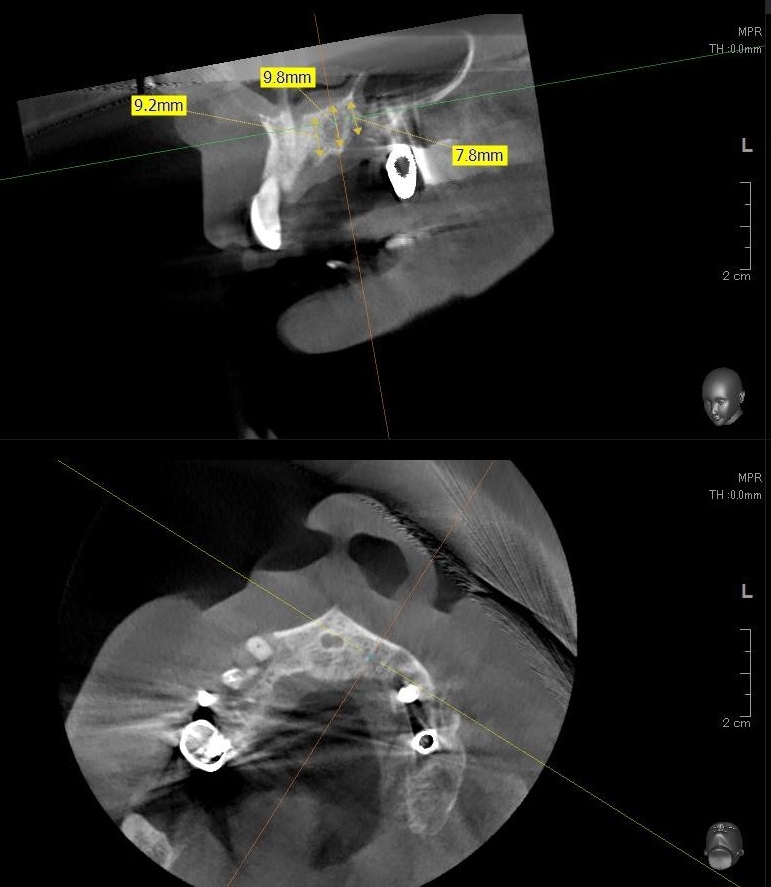

しっかりとインプラント埋め込まれた後は、動揺がないか、噛んだ時に当たらないかなどを確認して、最後にパノラマ写真を撮影して今回のオペは終了となりました。